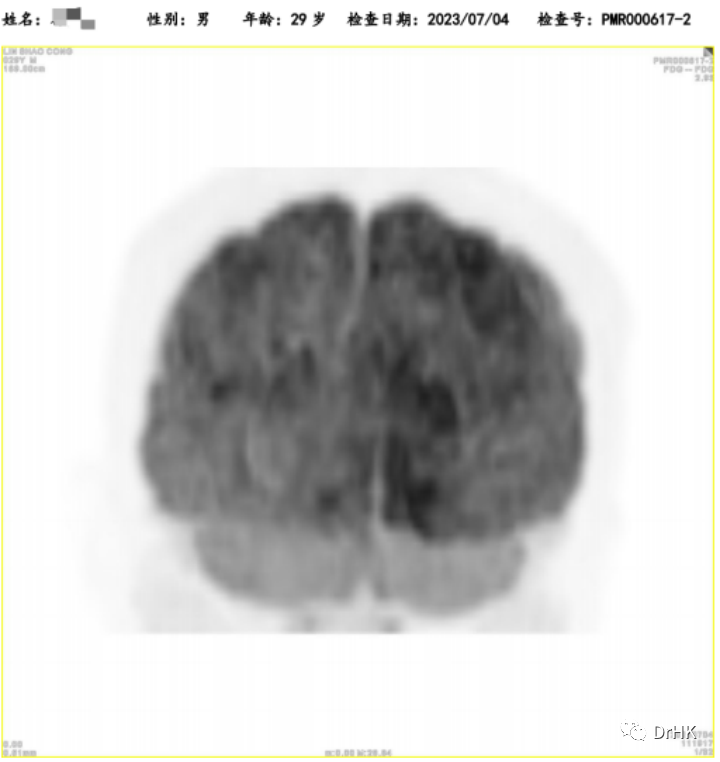

第一步治疗目标实现后,按计划开始了二次自体移植联合 CAR-T 细胞治疗的巩固治疗。本次我们采用了 TEAM 方案作为预处理(噻替哌+依托泊苷+阿糖胞苷+马法兰),并制备回输了 CD19/CD20 双靶点 CAR-T。治疗过程比较顺利,回输 CAR-T 细胞后 d5 天起开始出现发热,d8 天体温最高 39℃,诊断细胞因子释放综合征,判定 CRS 分级 I 级,ICANS 分级 0 级。检测到 CART 的扩增,患者粒细胞于自体造血干细胞回输后第 14(2022-07-05)天植活,血小板于自体造血干细胞输注后第 12 天(2022-07-03)植活。移植后我们给予患者口服奥布替尼作为维持治疗。

随后患者定期随访,分别于移植后半年、一年完善影像学评估。PET 如下图所示: